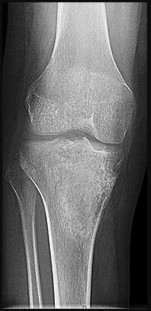

Figures 5a and 5b are the radiographs of a 74-year-old man with poorly differentiated squamous cell carcinoma of the lung. He has had an uneventful recovery after undergoing a wedge resection of his left upper lobe 6 months ago. He is experiencing left lateral knee pain, and a whole-body positron emission tomography/CT scan shows no avid area other than the lateral left distal femur. This patient has needed to use a wheelchair for 3 weeks because of his pain. You discuss these treatment options: aggressive curettage, local adjuvant treatment, cementation, and prophylactic fixation vs distal femoral resection and megaprosthesis total knee arthroplasty reconstruction. You should tell him that

Distal femoral megaprosthetic reconstruction after tumor resection is a reliable oncologic procedure, but 5-year implant survival is as low as 74% with an approximate 8% deep infection rate. The amputation rate is as high as 8% because of infection or recurrence, and there is an overall 18% revision rate. More than 10% of distal femoral megaprosthetic reconstructions are performed to address metastatic disease.

Fixation failure and infection may occur with either procedure. Radiation may not be recommended after a megaprosthesis reconstruction unless margins are not free of tumor. Either operation may be equally successful in returning patients to functional activities. Overall disease-free survival is related to the aggressiveness of the tumor and not the type of reconstruction performed.